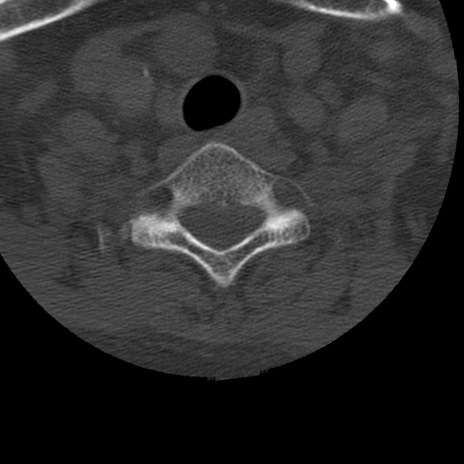

症例50 頚椎CT(横断像)

冠状断像